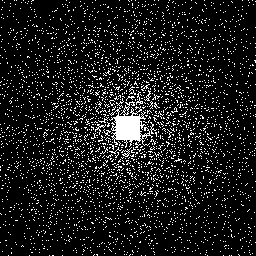

Magnetic Resonance Imaging (MRI) has excellent soft tissue contrast but is hindered by an inherently slow data acquisition process. Compressed sensing, which reconstructs sparse signals from incoherently sampled data, has been widely applied to accelerate MRI acquisitions. Compressed sensing MRI requires one or more model parameters to be tuned, which is usually done by hand, giving sub-optimal tuning in general. To address this issue, we build on previous work by the authors on the single-coil Variable Density Approximate Message Passing (VDAMP) algorithm, extending the framework to multiple receiver coils to propose the Parallel VDAMP (P-VDAMP) algorithm. For Bernoulli random variable density sampling, P-VDAMP obeys a "state evolution", where the intermediate per-iteration image estimate is distributed according to the ground truth corrupted by a zero-mean Gaussian vector with approximately known covariance. To our knowledge, P-VDAMP is the first algorithm for multi-coil MRI data that obeys a state evolution with accurately tracked parameters. We leverage state evolution to automatically tune sparse parameters on-the-fly with Stein's Unbiased Risk Estimate (SURE). P-VDAMP is evaluated on brain, knee and angiogram datasets and compared with four variants of the Fast Iterative Shrinkage-Thresholding algorithm (FISTA), including two tuning-free variants from the literature. The proposed method is found to have a similar reconstruction quality and time to convergence as FISTA with an optimally tuned sparse weighting and offers substantial robustness and reconstruction quality improvements over competing tuning-free methods.